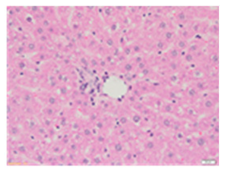

Liver wet weights of all rat groups showed no significant differences (Table 8). According to histochemical hematoxylin and eosin (H&E) staining, treatment with the highest dose of MPE (1000 mg/kg BW) did not result in morphological changes in the liver tissue (B) when compared with DI water treatment (A). Obviously, CCl4 induction (ip)/DI water treatment (po) caused hepatoxicity, which was indicated by a severe degree of fatty changes and fatty cysts in the liver tissue (C), whereas pretreatments of silymarin (100 mg/kg BW, po) effectively decreased the degree of fatty changes and fatty cysts in the liver when compared with the CCl4/DI water group. Indeed, MPE (250 and 1000 mg/kg BW, po) lowered the degree of lipid accumulation in the liver; inversely, MPE (500 mg/kg BW, po) exhibited a severe degree of lipid accumulation. Apparently, taking paracetamol (2 g/kg BW) induced a severe degree of hepatic necrosis when compared with rats that had not received the treatment. Similarly, pretreatments of silymarin (100 mg/kg BW, po) and MPE (250 and 1000 mg/kg BW, po) revealed a mild degree of hepatic necrosis, while MPE (500 mg/kg BW, po) revealed a moderate to severe degree of hepatic necrosis. Accordingly, the findings imply that the consumption of MPE (1000 mg/kg BW) was not harmful to the liver of healthy rats, while MPE (250 mg/kg BW) did improve fat deposition in the livers of CCl4-fed rats and offered protection against liver cell damage in paracetamol-fed rats.

Wet weight values (mean ± SD) and H&E staining of liver from rats with hepatotoxicity induced by CCl4 and paracetamol.